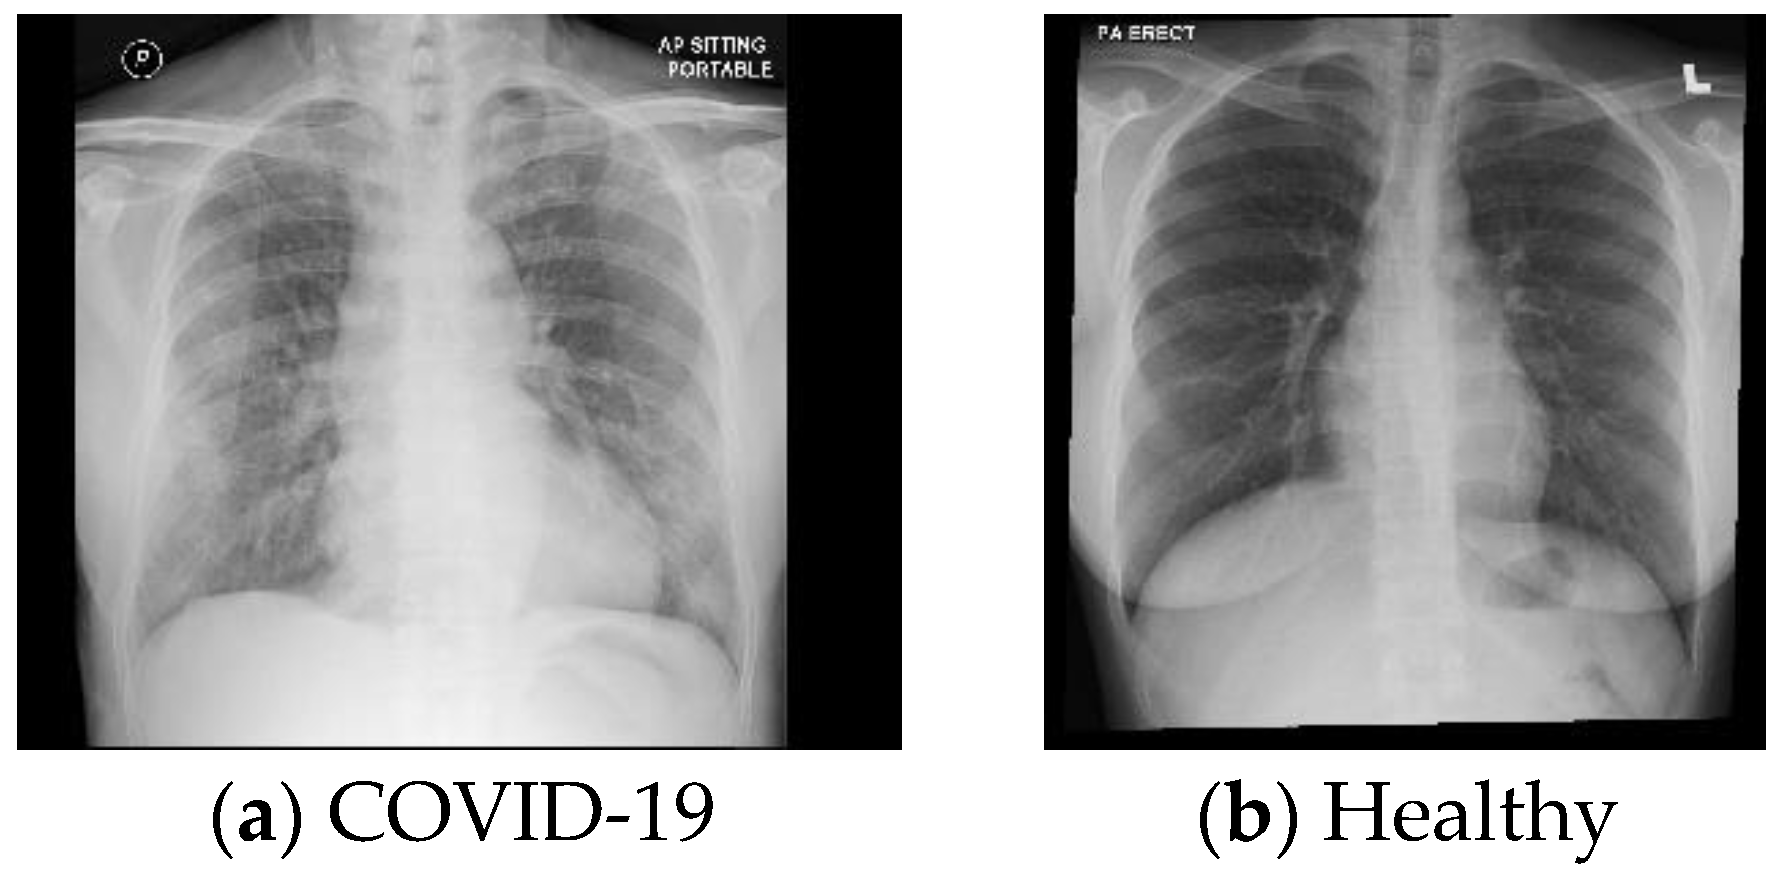

2.1.1. The First Database (DB1)

2.1.2. The Second Database (DB2)

2.1.3. The Third Database (DB3)

2.1.4. The Fourth Database (DB4)